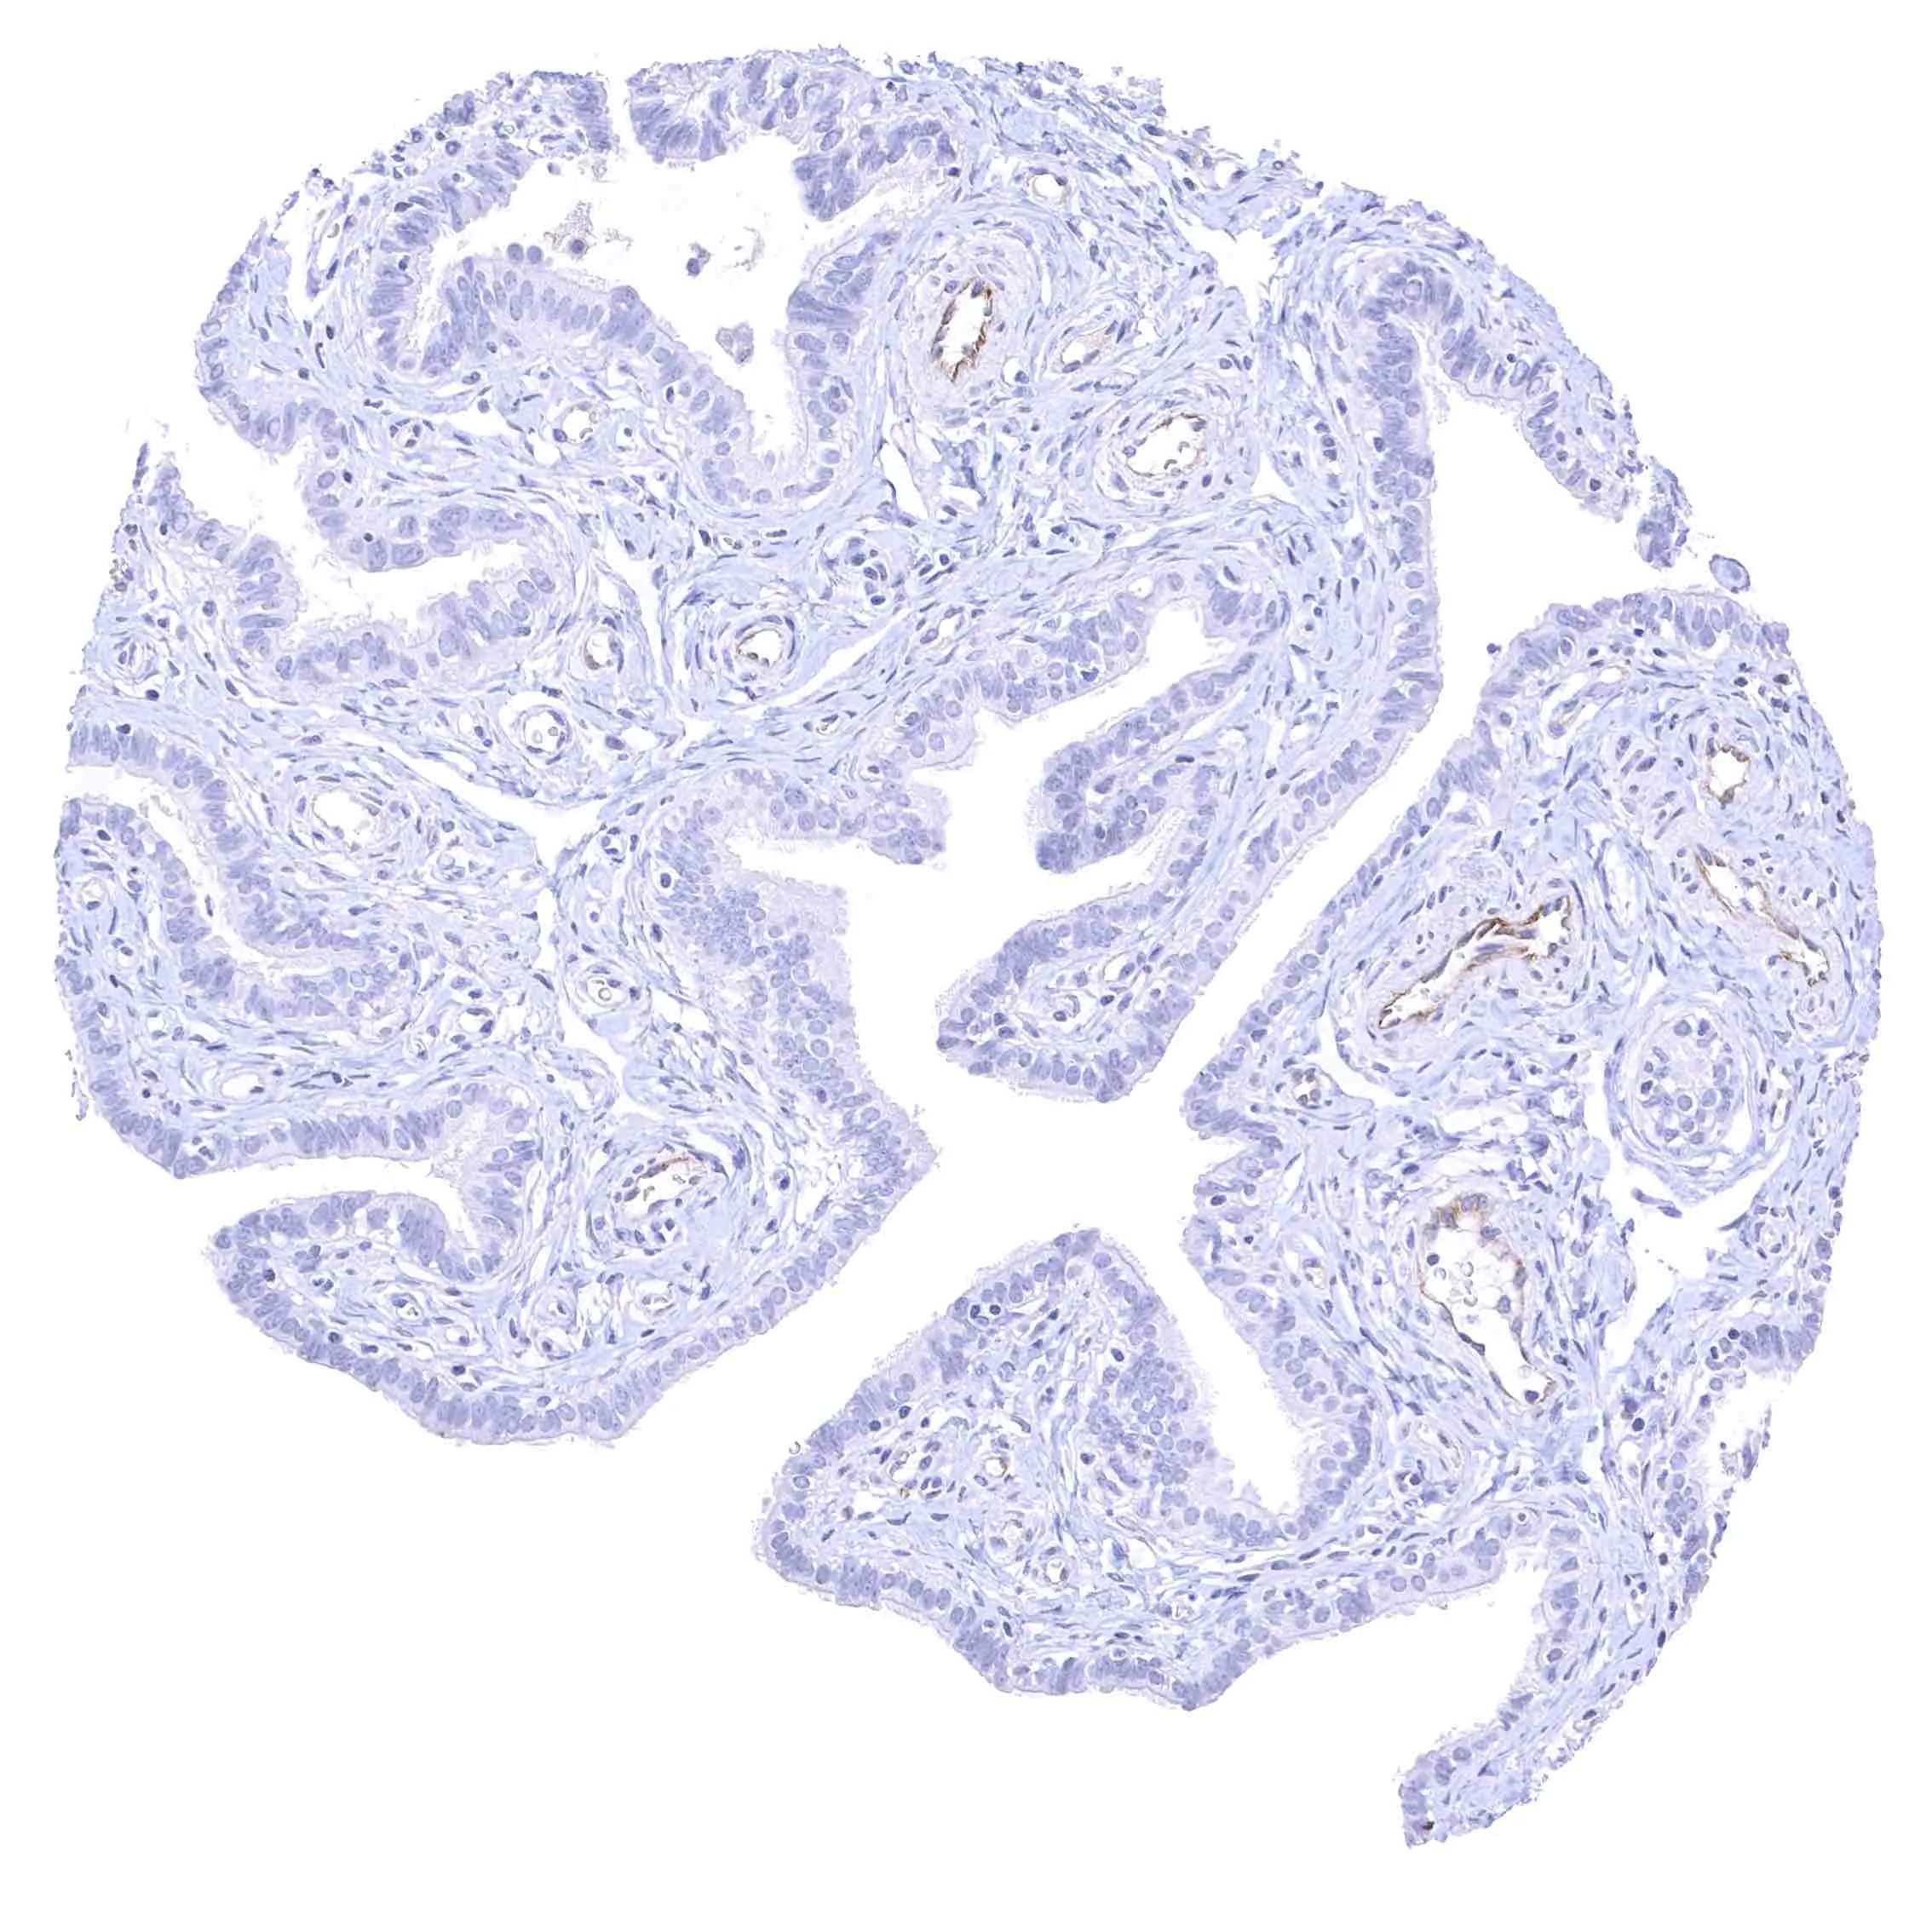

Uterus, endocervix